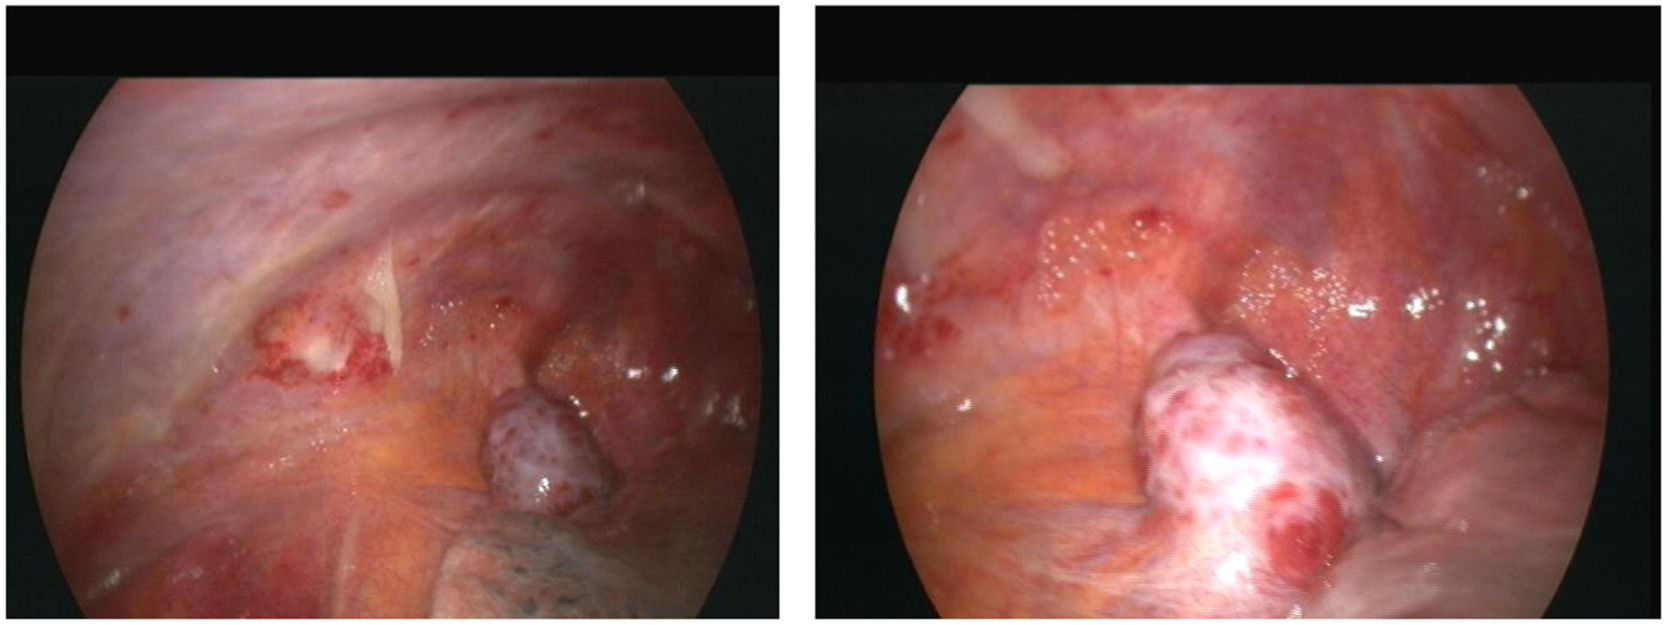

To confirm the cause of the mediastinal lesion, the patient underwent medical thoracoscopy. A hypervascular, sessile mass was observed in the prevascular mediastinum and subsequently biopsied (Fig. 2). The tumour was not separated from the aorta during the procedure. Histological examination of pleural fragments showed vascular congestion, alveoli filled with macrophages, and compression of the alveoli by a fibroadipose tissue 'mass' (MDM2-) and smooth muscle (actin+), accompanied by capillary proliferation (CD34+). Thrombi were frequently present. No necrosis or mitoses were detected. Histochemical investigation for microorganisms, including PAS, Ziehl-Neelsen, and Grocott staining, yielded negative results. Immunohistochemical analysis was performed to explore other neoplasms, and results for calretinin, BER-EP4, S100, CD1a, Melan-A, HMB45, and p53 were negative (Fig. 3)